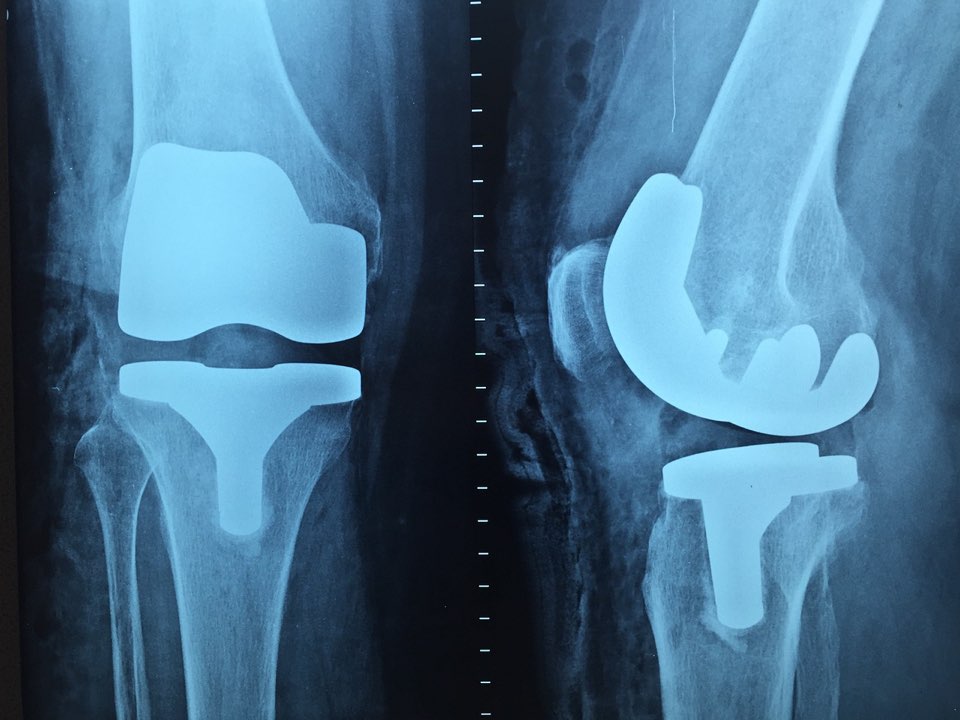

증상이 심해지면 기본적인 동작에서 통증을 너무 많이 느껴 일상생활이 힘들 정도로 심한 경우가 대부분입니다. 노인층에서는 이러한 무릎 통증의 원인으로 무릎 건강이 나빠져 생활 반경이 좁아지고 결국 연골 치료 무릎인공관절 수술을 하시는 경우가 급격히 늘어나고 있습니다.